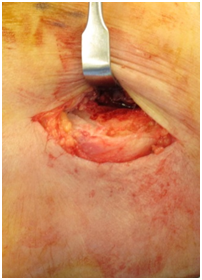

1. Arthroscopic or open65–68 Mini open including Nirschl technique69,70 Long term results of arthroscopic release.71 The arthroscopic release is the commonest form of operative management in our practice (Figures 36).

Figure 3 Lateral epicondylitis as viewed through the anteromedial portal.